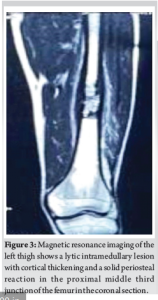

On physical examination, there was a tender, ill-defined swelling over the anterolateral aspect of the left mid-thigh. Skin over the swelling was normal. The range of motion of the left hip and knee was normal, with no distal neurovascular deficit. Initial X-ray showed features of an osteolytic intramedullary lesion at the junction of middle and distal third of left femur with surrounding sclerosis and periosteal reaction (Fig. 1). Magnetic resonance imaging (MRI) and computed tomography (CT) of left thigh showed lytic intramedullary lesion, with cortical thickening and a solid periosteal reaction, suspicious for osteomyelitis or Langerhans cell histiocytosis (Fig. 2 and 3). Based on clinical features, radiographs, and higher imaging, we had a suspicion of osteomyelitis/tumor. Since radiographs showed sclerosis and periosteal reaction, we strongly suspected Ewing’s sarcoma. Hence, CT-guided biopsy (Fig. 4) was done, which showed bone remodeling with increased osteoclastic giant cells suggestive of chronic osteomyelitis. To obtain deep cultures and since we still had a strong suspicion of malignancy, an open biopsy was planned. Open biopsy was done through a cortical defect enlarged to a window at the site of lesion (Fig. 5). However, the biopsy report showed only necrotic bone with scattered chronic inflammation, focal fibrosis, and osteoclastic giant cells suggestive of chronic osteomyelitis (Fig. 6). Culture sensitivity was done in which no organism was isolated.